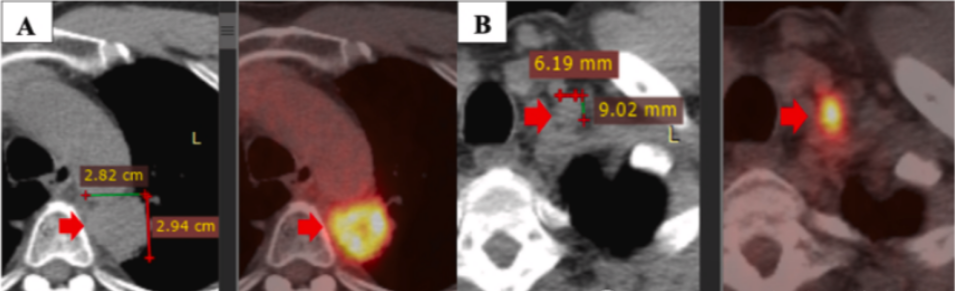

经过一个疗程共6次的NK细胞输注,同步配合吉西他滨和贝伐单抗用药后,患者的原发肿瘤以及转移灶的体积均有显著缩减。更为重要的是,生活质量监测数据显示患者的生活质量得到了明显改善。在整个联合干预过程中,未观察到明显的副作用,尤其是对造血系统、肝脏以及肾脏功能未产生毒性影响。

这一病例生动证明了NK细胞联合贝伐单抗及吉西他滨疗法在应对PD-L1表达阳性的晚期非小细胞肺癌患者时,可能是一种颇具前景的有效干预策略。

在6次输注NK细胞联合吉西他滨、贝伐珠单抗后,患者的原发性和转移性病灶明显缩小,生活质量明显改善。此外,在联合治疗期间,没有副作用的报道,也没有在造血系统、肝脏和肾脏中观察到毒性。病例表明,这种治疗方案是PD-L1表达的晚期非小细胞肺癌的一种潜在治疗方法。